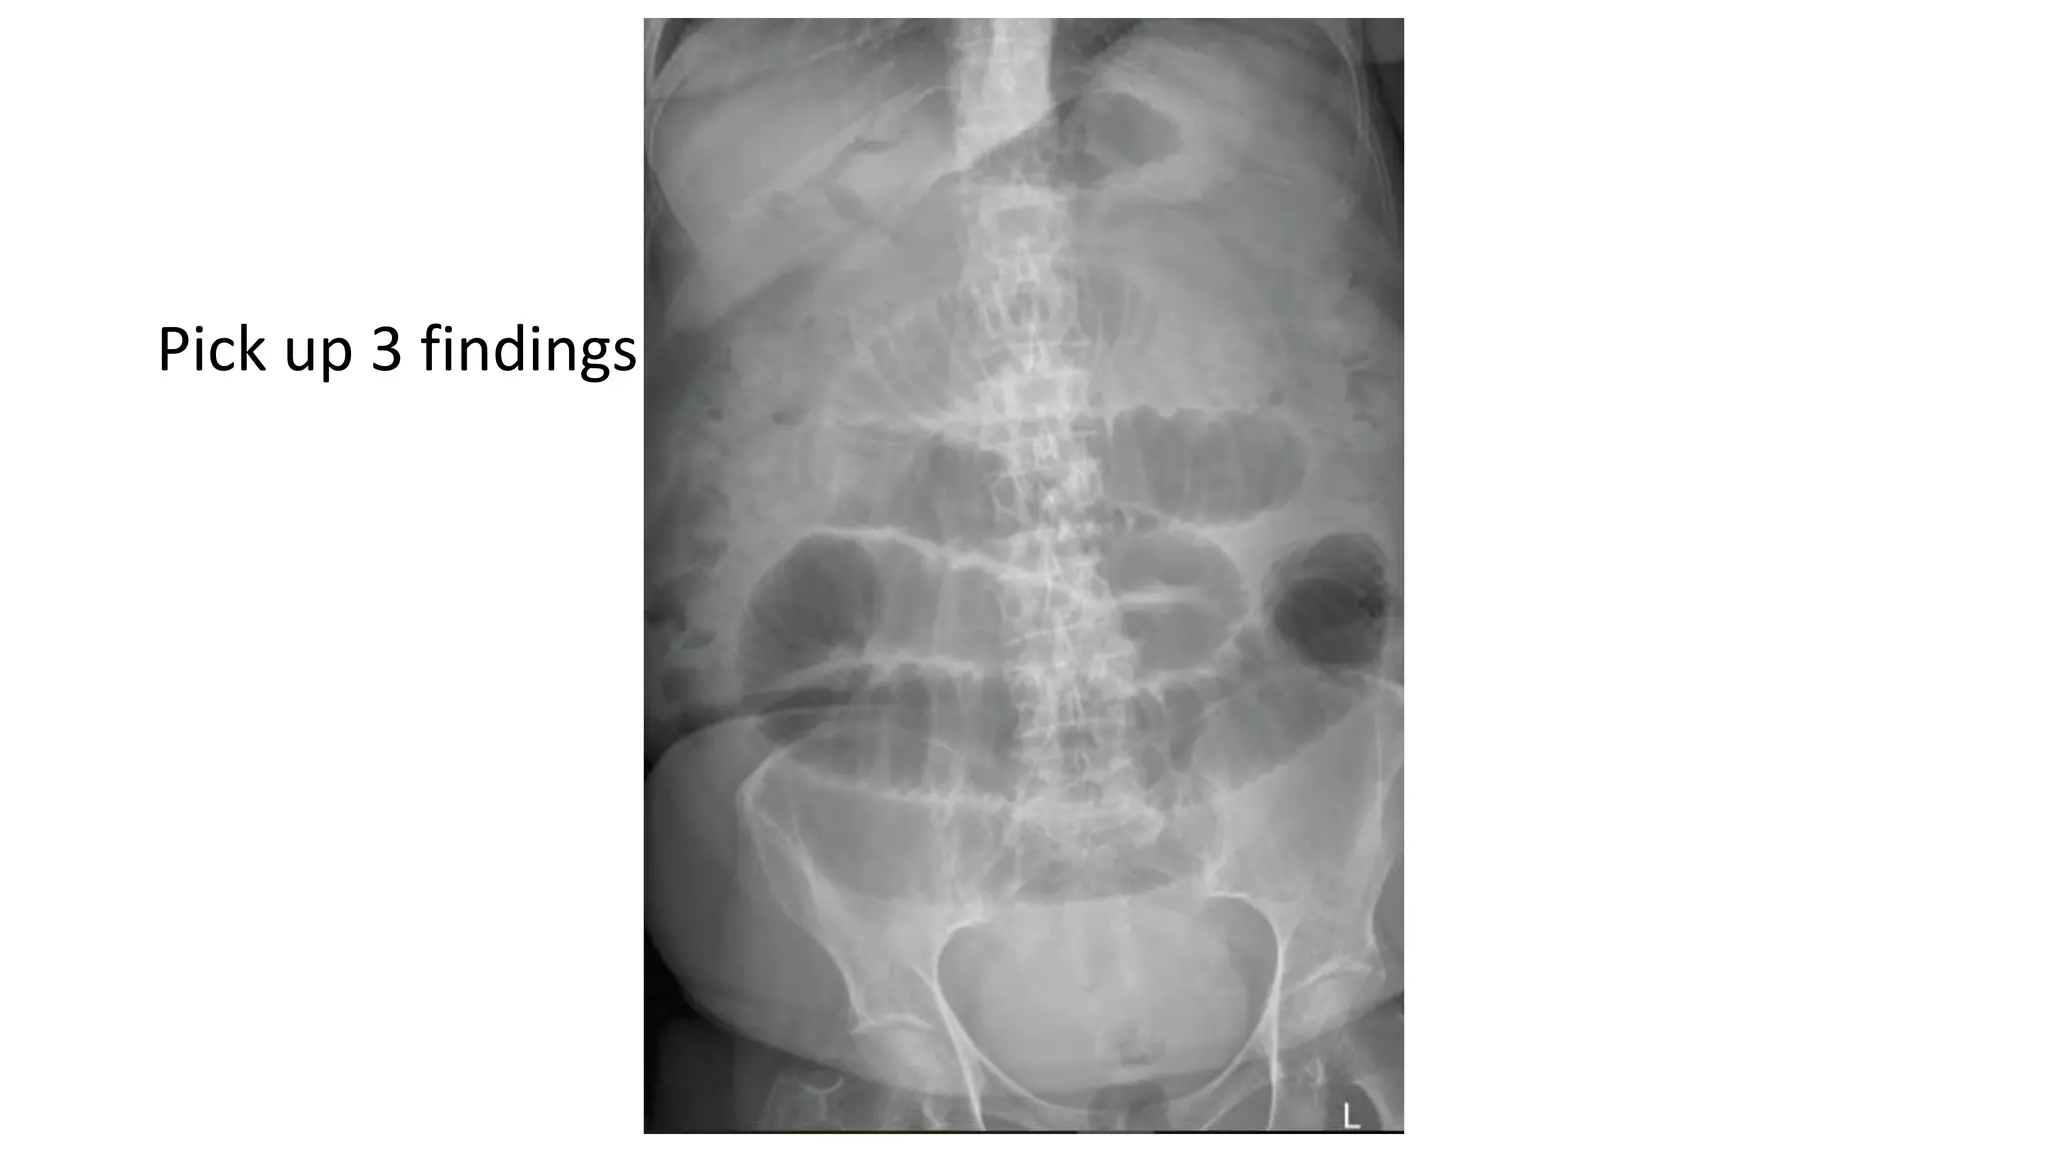

Who wants tobe a hero ?

• 62.

Pick up 3findings

• 65.